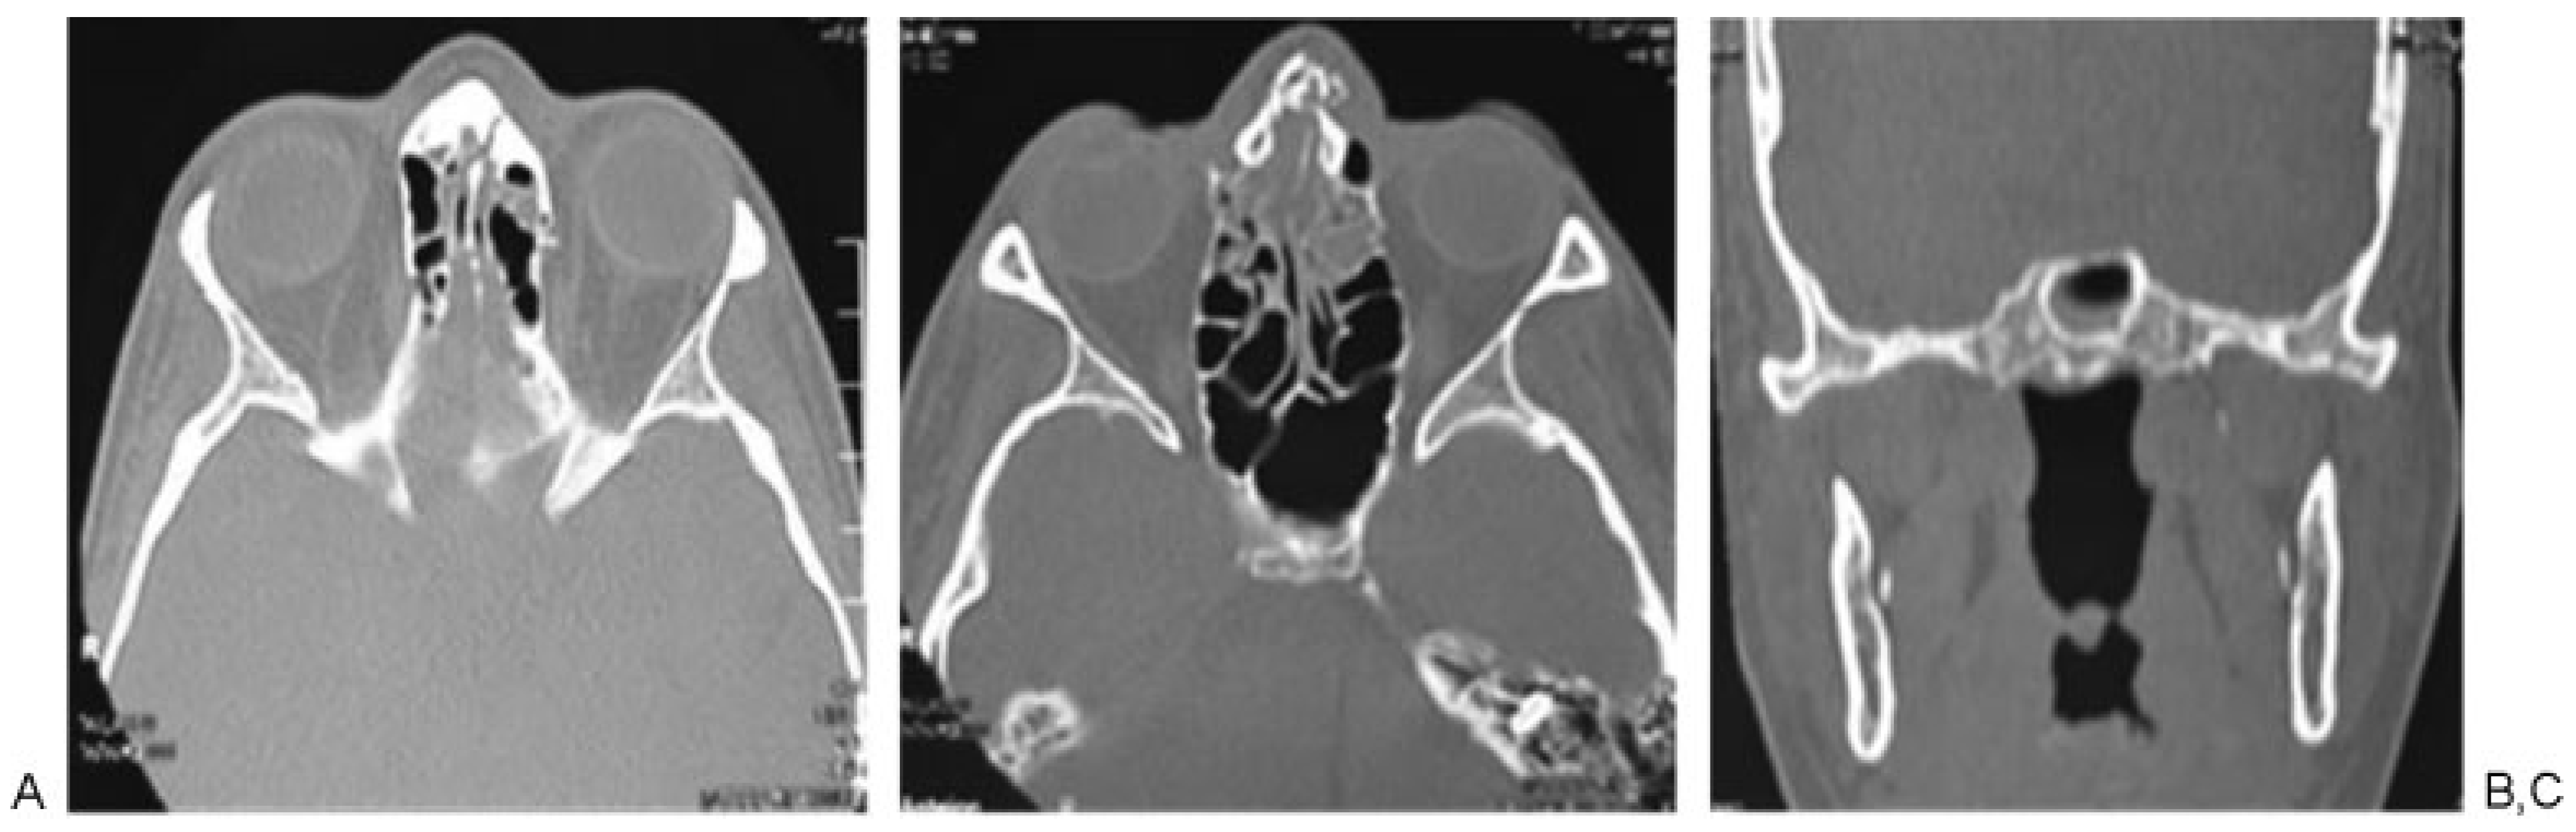

Figure 4. Patient 3: slightly displaced malar fracture in a patient with medium energy trauma, (A) presence of fracture at the level of the zygomatic arch, (B and C) fracture at the lateral wall of the sphenoid bone and orbital fracture associated.

According to Manson’s classification, 17.9% (n ¼ 38) of the trauma in the group corresponded to high-energy trauma, followed by medium-energy trauma at 33.5% (n ¼ 71) and low-energy trauma at 48.6% (n ¼ 103). Among the patients with high-energy trauma, 31.5% (n ¼ 12) had combined fractures of the sphenoid bone and sphenoid sinus and 31.5% (n ¼ 12) had sphenoid sinus fractures only. In contrast, 1.4% (n ¼ 3) of patients with middle-energy trauma had sphenoid bone fractures, 5.6% (n ¼ 4) of the patients had sphenoid sinus fractures, and 4.2% (n ¼ 3) of the patients had sphenoid bone and sphenoid sinus fractures. In the low-energy trauma group, only 1 patient presented sphenoid sinus fracture (0.97%; Table 3; Figure 2, Figure 3 and Figure 4).